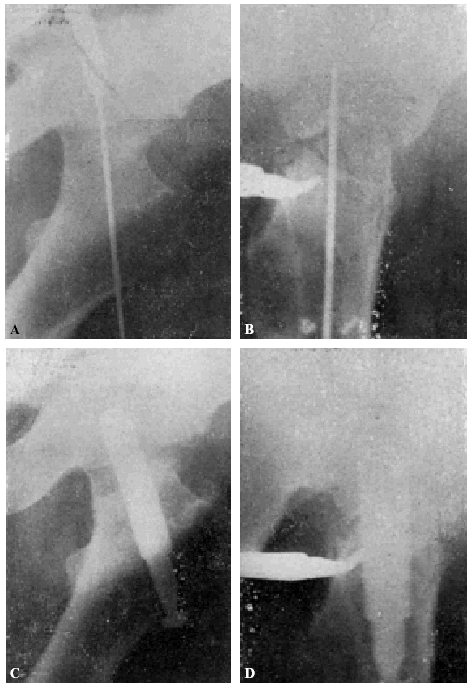

Muchos fracasos de Böhler se deben a haber cargado precozmente la extremidad. La figura 15, A y B8, corresponde a un fracturado operado por Böhler. El clavo está bien colocado en las dos proyecciones, aunque es poco profundo y ligeramente ventral en lugar de dorsal. A los dos meses, cuando el enfermo andaba perfectamente bien, nota el enfermo bruscamente dolores y se comprueba a la exploración radiográfica que el clavo se había salido de la cabeza del fémur (fig. 15, C y D). Dice Böhler, referente a este caso: «Este desprendimiento no habría ocurrido si el clavo se hubiera colocado algo más caudal y más dorsal respecto a la línea media del cuello y de la cabeza y, a la vez, hubiese penetrado lo suficiente en ésta». Y añadimos nosotros: a pesar de que la situación del clavo no era idealmente perfecta en este caso, la culpa del fracaso reside fundamentalmente en la carga precoz del miembro fracturado. Si observamos la figura 16, A y B (observación núm. 23), aunque en proyección anteroposterior, la situación del clavo puede considerarse perfecta; en proyección lateral, está en situación mucho más ventral que la observación anterior de Böhler, y sin embargo la enferma, operada en mayo de 1941, anda en la actualidad, a pesar de sus setenta y ocho años, sin la ayuda de ningún bastón y sin presentar ninguna molestia (fig. 16 C). La situación del clavo en este caso es muy semejante a la de la enferma citada anteriormente, que falleció al extraerle el clavo intolerante (supuración de la herida, sin síntomas generales de infección) (fig. 17 A y B; obs. núm. 18), por lo que todo hace suponer que, en caso de no haberse presentado el desenlace fatal, el resultado funcional hubiera sido bueno.

Figura 15. A: comprobación roentgenológica después de colocar el clavo e impactar los fragmentos. La diástasis entre éstos ha desaparecido. El clavo está en el centro del cuello y de la cabeza, pero no lo suficiente profundo, puesto que su punto dista 13 mm. de la superficie de la cabeza, en vez de 3 a 6 mm. B: en la proyección lateral, el clavo está colocado algo hacia delante, es decir, demasiado ventral, en la cabeza del fémur. (De Böhler Jeschke.)

Figura 15. C y D: al principio andaba perfectamente, pero de pronto se le presentaron dolores, y en la roentgenografía se vio que el clavo se había salido de la cabeza del fémur y los fragmentos habían vuelto a desviarse a la posición que tenían antes de la reducción. Este desprendimiento no habría ocurrido si el clavo se hubiera colocado algo más caudal y más dorsal respecto a la línea media del cuello y de la cabeza, y, a la vez, hubiese penetrado lo suficiente en ésta. (De BöhlerJeschke.)

Figura 16. A: obs. núm. 23. La situación del clavo en esta proyección es buena. B: obs. núm. 23. El mismo caso de la figura anterior, en proyección lateral. La situación del clavo es excesivamente ventral. C: Obs. núm. 23. El mismo caso de la figura anterior, en la actualidad. A pesar de la artro-sis existente, la enferma no presenta la más mínima molestia ni se halla limitada la movilidad articular.

Figura 17. obs. núm. 18. La fractura está enclavada en valgus. El clavo está bien colocado, aunque es algo corto. B: obs. núm. 18. El mismo caso de la figura anterior, en posición lateral. El clavo, algo corto, está colocado en la misma posición defectuosa que el caso de la figura 16, B.